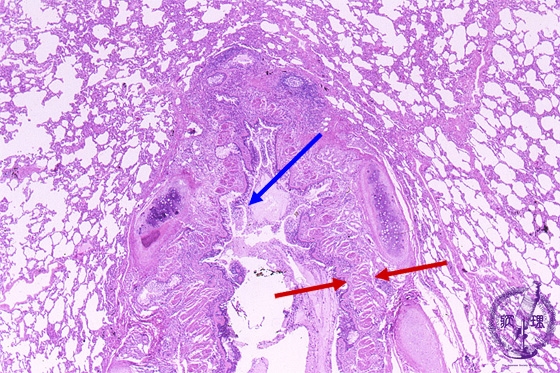

- 5.Lung, Pleura

- (6)Bronchial asthma

Microscopic view (HE stain, low power view): Bronchial wall smooth muscle (red arrow) proliferates with thickening of the entire bronchial wall. Mucus retention (blue arrow) is noted within the bronchial lumen.